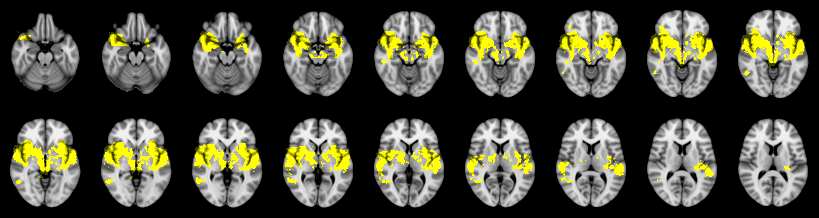

Pain study, Cluster extent, Corrected

Not combined

Combined

Fisher: